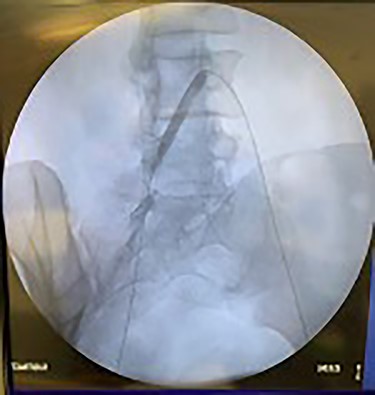

Catheter arteriogram results showed significant occlusion of the left iliac artery (Figs 3 and 4), the right iliac artery (Fig. 1), as well as the distal abdominal aorta (Fig. 2). There were numerous collateral vessels noted, indicating the presence of long-standing proximal stenosis (Fig. 1). The decision was made to use angioplasty to help widen the areas of stenosis. An 8 mm × 40 mm Passeo balloon was advanced from the right femoral artery into the left iliac artery (Fig. 7) and insufflated to 6 mmHg (Fig. 6). The balloon was allowed to remain expanded for 1 min and then was deflated. Next, the distal aorta was repaired in a similar fashion. The balloon was advanced into the distal aorta from the right femoral access and insufflated to 12 mmHg (Fig. 8). The balloon was allowed to remain expanded for 90 s.

Fluoroscopy of bilateral iliac arteries showing significant arterial disease.